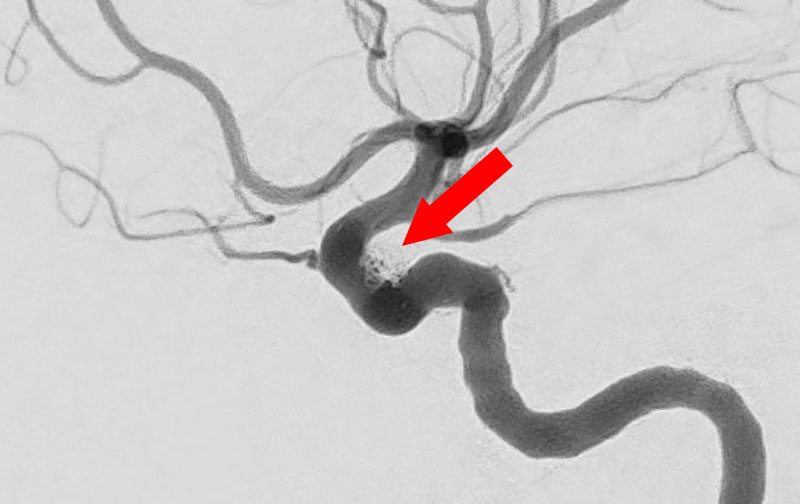

くも膜下出血

右内頚動脈脳動脈瘤破裂

40代

救急外来

No.1131 手術中